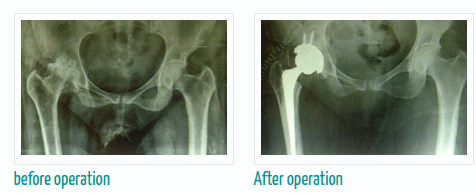

जरी संधिवात शरीराच्या सर्व सांध्यांवर परिणाम करत असेल तरी देखील त्याचा सर्वात जास्त परिणाम गुडघ्यांवर होतो ज्यामुळे त्यांच्या सांध्यांना सूज आणि तीव्र वेदना होऊ शकतात. ज्यामुळे त्यांना गुडघेदुखी ची समस्या उद्भवू शकते. यावर एकच उपाय आहे ते म्हणजे संधिवात झाल्यास शस्त्रक्रिया करावी.